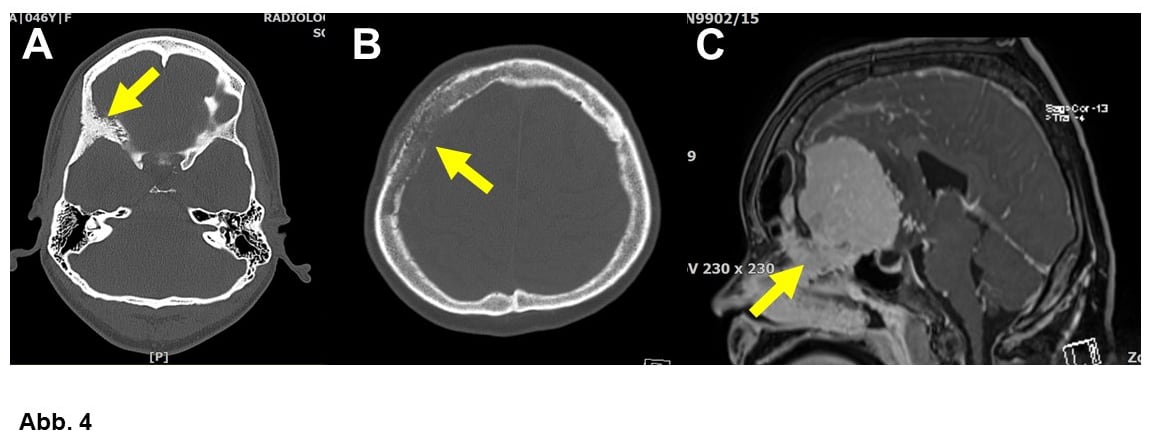

Von großer klinischer Bedeutung ist die Einteilung nach Lokalisation. Am häufigsten wachsen Meningeome ausgehend von der Hirnhaut über den Hemisphären (= Hirnhälften, Konvexitätsmeningeome, Abb. 1A-C) oder im Bereich einer bindegewebigen Sichel zwischen den Hemisphären (Falxmeningeom, Abb. 1C und D). Sogenannte Schädelbasismeningeome (Abb. 2, 3 und 4C) sind wegen ihrer Lage häufig schwieriger zu operieren als Konvexitäts- und Falxmeningeome. Meningeome können nicht nur ausgedehnt in den Hirnhäuten, sondern auch im Knochen (Abb. 4A und B) oder sogar vom Knochen ausgehend in die umgebenden Weichteile einwachsen (Abb. 4C). Meningeome im Bereich der Wirbelsäule (Abb. 5) sind seltener als im Kopf, sind aber umgekehrt häufige Tumoren im Rückenmarkskanal, wo sonst Tumoren eher selten sind. Bei bis zu 20% der Patienten liegen mehrere Meningeome vor (Abb. 1C).

Ca. 10 bis 20% aller Meningeome wachsen überdurchschnittlich schnell bzw. häufig trotz Behandlung wieder nach. Die Neuropathologie unterscheidet zwischen den häufigen WHO-Grad I (gutartig), den selteneren WHO Grad II (Abb. 4B und 6A) und den sehr seltenen und klinisch bösartigen anaplastischen Meningeomen WHO Grad III (Abb. 6B). Es gibt verschiedene histologische Typen (= unterschiedliche Erscheinungsbilder unter dem Mikroskop), was aber meist für die Klinik keine Rolle spielt. Einige wenige Tumoren werden allerdings aufgrund ihrer Histologie den WHO Graden II oder sogar III zugeordnet.

Meningeome treten häufiger bei Frauen als bei Männern auf, das ist bei Meningeomen der Wirbelsäule besonders auffällig (Abb. 5). Eine überzeugende Erklärung dafür gibt es nicht. Männer erkranken relativ häufiger an WHO Grad II- oder III-Tumoren (Abb. 4B, 6A und B). Ionisierende Strahlung gilt als wichtiger Risikofaktor, so haben zum Beispiel Patienten, die als Kinder bei Leukämie eine Schädelbestrahlung erhalten haben, ein vielfach erhöhtes Risiko, an einem Meningeom zu erkranken. Welche Genmutationen (Veränderungen der Erbsubstanz) zur Meningeomentstehung führen, ist derzeit Gegenstand intensiver Forschung. Es konnten bereits mehrere Meningeomgene identifiziert werden und man muß damit rechnen, dass solche Befunde zukünftig ähnlich wie bei den Gliomen für die Diagnostik und Behandlung von Meningeomen wichtig werden. Vererbt werden diese Veränderungen aber nicht.

Viele Meningeome kann man schon mittels CCT diagnostizieren, als Goldstandard gilt aber die MR-Tomographie. Knochenbefall (Abb. 4A und B) ist allerdings im CCT besser zu beurteilen. Manchmal hilft es bei einer Operation bzw. Operationsplanung, wenn auch eine Angiographie (Gefäßdarstellung) vorliegt, die genau die Lagebeziehungen zwischen einem Meningeom und großen Blutgefäßen bzw. die Blutflußverhältnisse zeigt.

A. Typischer Knochenbefall (Pfeil), 46-jährige Frau.

B. Konvexitätsmeningeom mit ausgedehntem Knochenbefall (69-jähriger Patient, Pfeil). Bei diesem Patienten lag ein atypisches Meningeom WHO-Grad II vor. Im Rahmen der Operation mußte der Knochen entfernt und durch ein Implantat ersetzt werden.

C. 22-jährige Patientin mit einem großen Schädelbasismeningeom, das in die Nase einwächst (Pfeil).